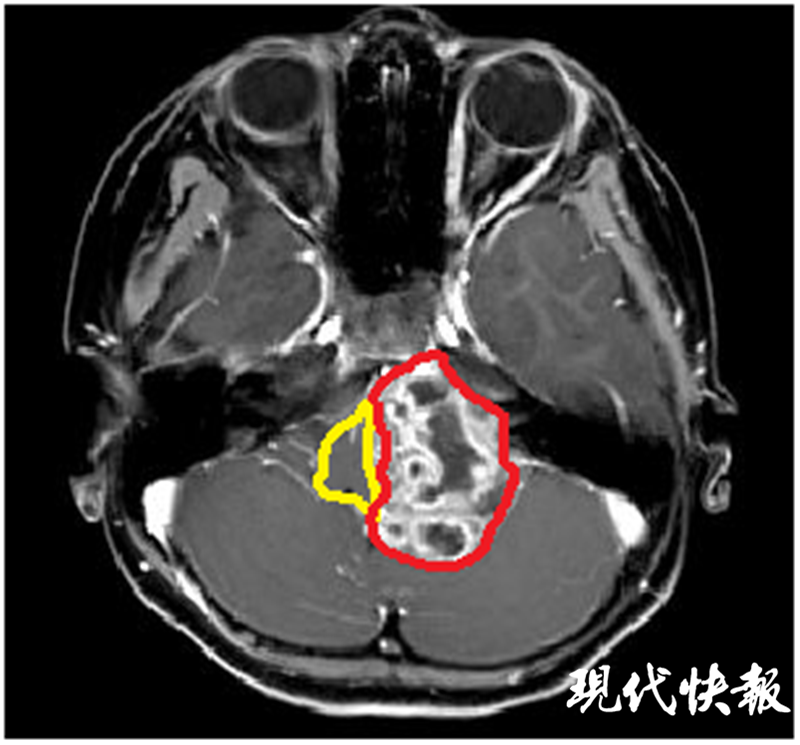

時(shí)間推回到一個(gè)月前,剛滿6歲的諾諾突然直喊頭痛,并伴隨頻繁嘔吐。當(dāng)?shù)蒯t(yī)院首先給諾諾進(jìn)行了消化道的檢查,未見(jiàn)異常。但進(jìn)一步的顱腦核磁共振檢查卻發(fā)現(xiàn)后腦部位長(zhǎng)了一個(gè)巨大腫瘤,腦干與小腦已嚴(yán)重受壓變形。

△術(shù)前核磁共振:黃色標(biāo)記為腦干,紅色標(biāo)記為腫瘤

因當(dāng)?shù)蒯t(yī)院無(wú)法治療,諾諾父母找到了位于揚(yáng)州的蘇北人民醫(yī)院,向神經(jīng)外科張恒柱教授尋求幫助。經(jīng)過(guò)仔細(xì)檢查發(fā)現(xiàn),諾諾顱內(nèi)的腫瘤長(zhǎng)徑達(dá)6cm,如雞蛋大小,腦干已被壓縮至正常的1/5,需要盡快手術(shù)治療。但巨大的腫瘤與腦干、小腦緊緊粘連,侵犯左側(cè)后腦幾乎所有的重要血管和神經(jīng),稍有不慎都會(huì)導(dǎo)致嚴(yán)重后果。從影像檢查看,諾諾顱內(nèi)腫瘤明顯血管豐富,手術(shù)時(shí)很可能伴隨大出血,而兒童對(duì)于出血的耐受能力遠(yuǎn)低于成人。